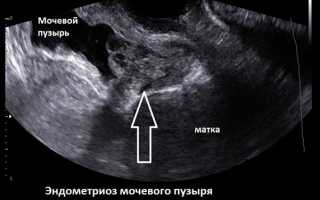

Эндометриоз мочевого пузыря – заболевание мочевыделительной системы, при котором эндометрий матки распространяется на мочевой пузырь.

• УЗИ (определяется состояния мочевого пузыря, выявляются очаги поражения);